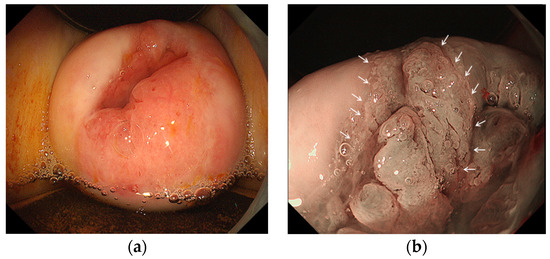

2.2. Colposcopic Procedure

2.3. Endoscopic Procedure